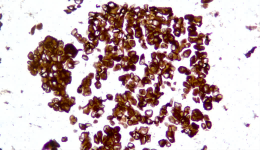

| Description | CLDN18.2是Claudin蛋白質(zhì)家族的一員,位于細(xì)胞膜表面,Claudin18.2(CLDN18.2)表達(dá)具有特異性。其作為Claudins蛋白的一個(gè)亞型,在正常組織中僅表達(dá)于分化的胃黏膜上皮細(xì)胞。在胃癌、食管癌和胰腺癌等多種腫瘤中表達(dá),并且不僅限于原發(fā)病灶,在轉(zhuǎn)移灶中也有表達(dá)。目前臨床研究中使用的檢測(cè)方法均為免疫組化。 |

| 示例 | ![]() |

| IHC染色結(jié)果 | |